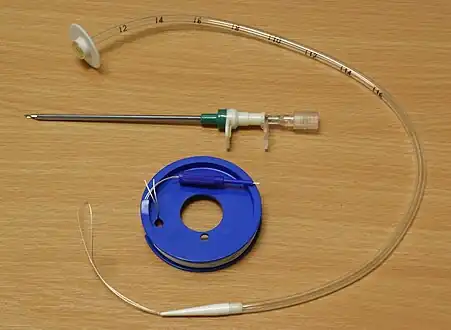

In the Russell introducer technique, the Seldinger technique is used to place a wire into the stomach, and a series of dilators are used to increase the size of the gastrostomy. The tube is then pushed in over the wire.[7]